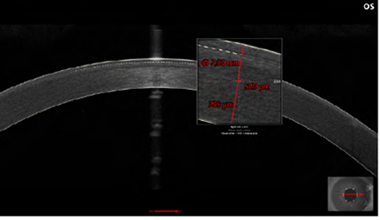

정확한 전안부 측정 (전방각 거리, 전방 깊이, 홍채 모양)이 가능하며, 조절력에 의한 구조적 변화를 예측하여 개인에 가장 적합한 렌즈 선택이 가능합니다. 또한 수술 후에는 삽입된 렌즈의 위치를 정확히 측정하여 렌즈로부터 각막 및 수정체까지의 거리를 측정할 수 있어 수술 후 정확하게 수술결과를 평가할 수 있습니다.

눈의 구조적 변화에 따른 렌즈 안전 거리 예측